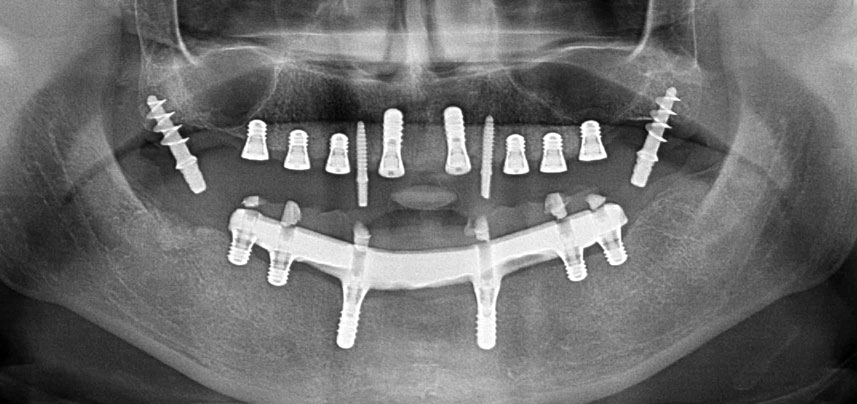

Tres años después, llegó el momento de colocar una prótesis del mismo tipo en el maxilar superior. Basándose en una planificación mediante tomografía computarizada de haz cónico (CBCT, por sus siglas en inglés), se evitó la necesidad de realizar una elevación del seno utilizando implantes cortos, mientras que una plantilla quirúrgica sirvió para transferir las posiciones planificadas al borde alveolar (figuras 1 y 2).

Fig. 1: Vista preoperatoria del borde maxilar, con las posiciones del implante marcadas con la ayuda de una plantilla quirúrgica de plástico. Debido a la baja altura del borde, se planificaron implantes posteriores supercortos.

Pantomografía posoperatoria

Fig. 10: La pantomografía posoperatoria muestra todos los implantes en posiciones correctas, incluidos los implantes provisionales pterigoideos.